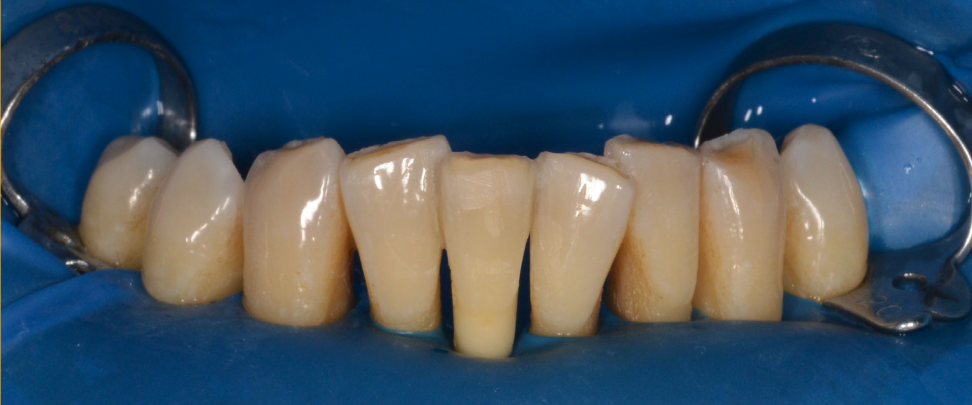

Având în vedere că se folosește un sistem adeziv, dinții se izolează cu diga dentară, care are rolul unei izolări perfecte de restul mediului bucal și reduce contaminarea cu salivă sau sânge. Dinților extrași sau pierduți li se reduce din lungimea rădăcinii, pentru a putea fi repozitionați estetic în poziția corectă. Ei nu mai primesc vascularizație și inervație, doar se sprijină la nivelul gingiei. (Fig. 5.4.3).

Banda de imobilizare are culoarea aproximativă cu cea a dinților, singurul inconvenient fiind volumul ușor mărit cu care pacientul se obișnuiește în 1-2 zile. (Fig. 5.4.4 și 5.4.5).